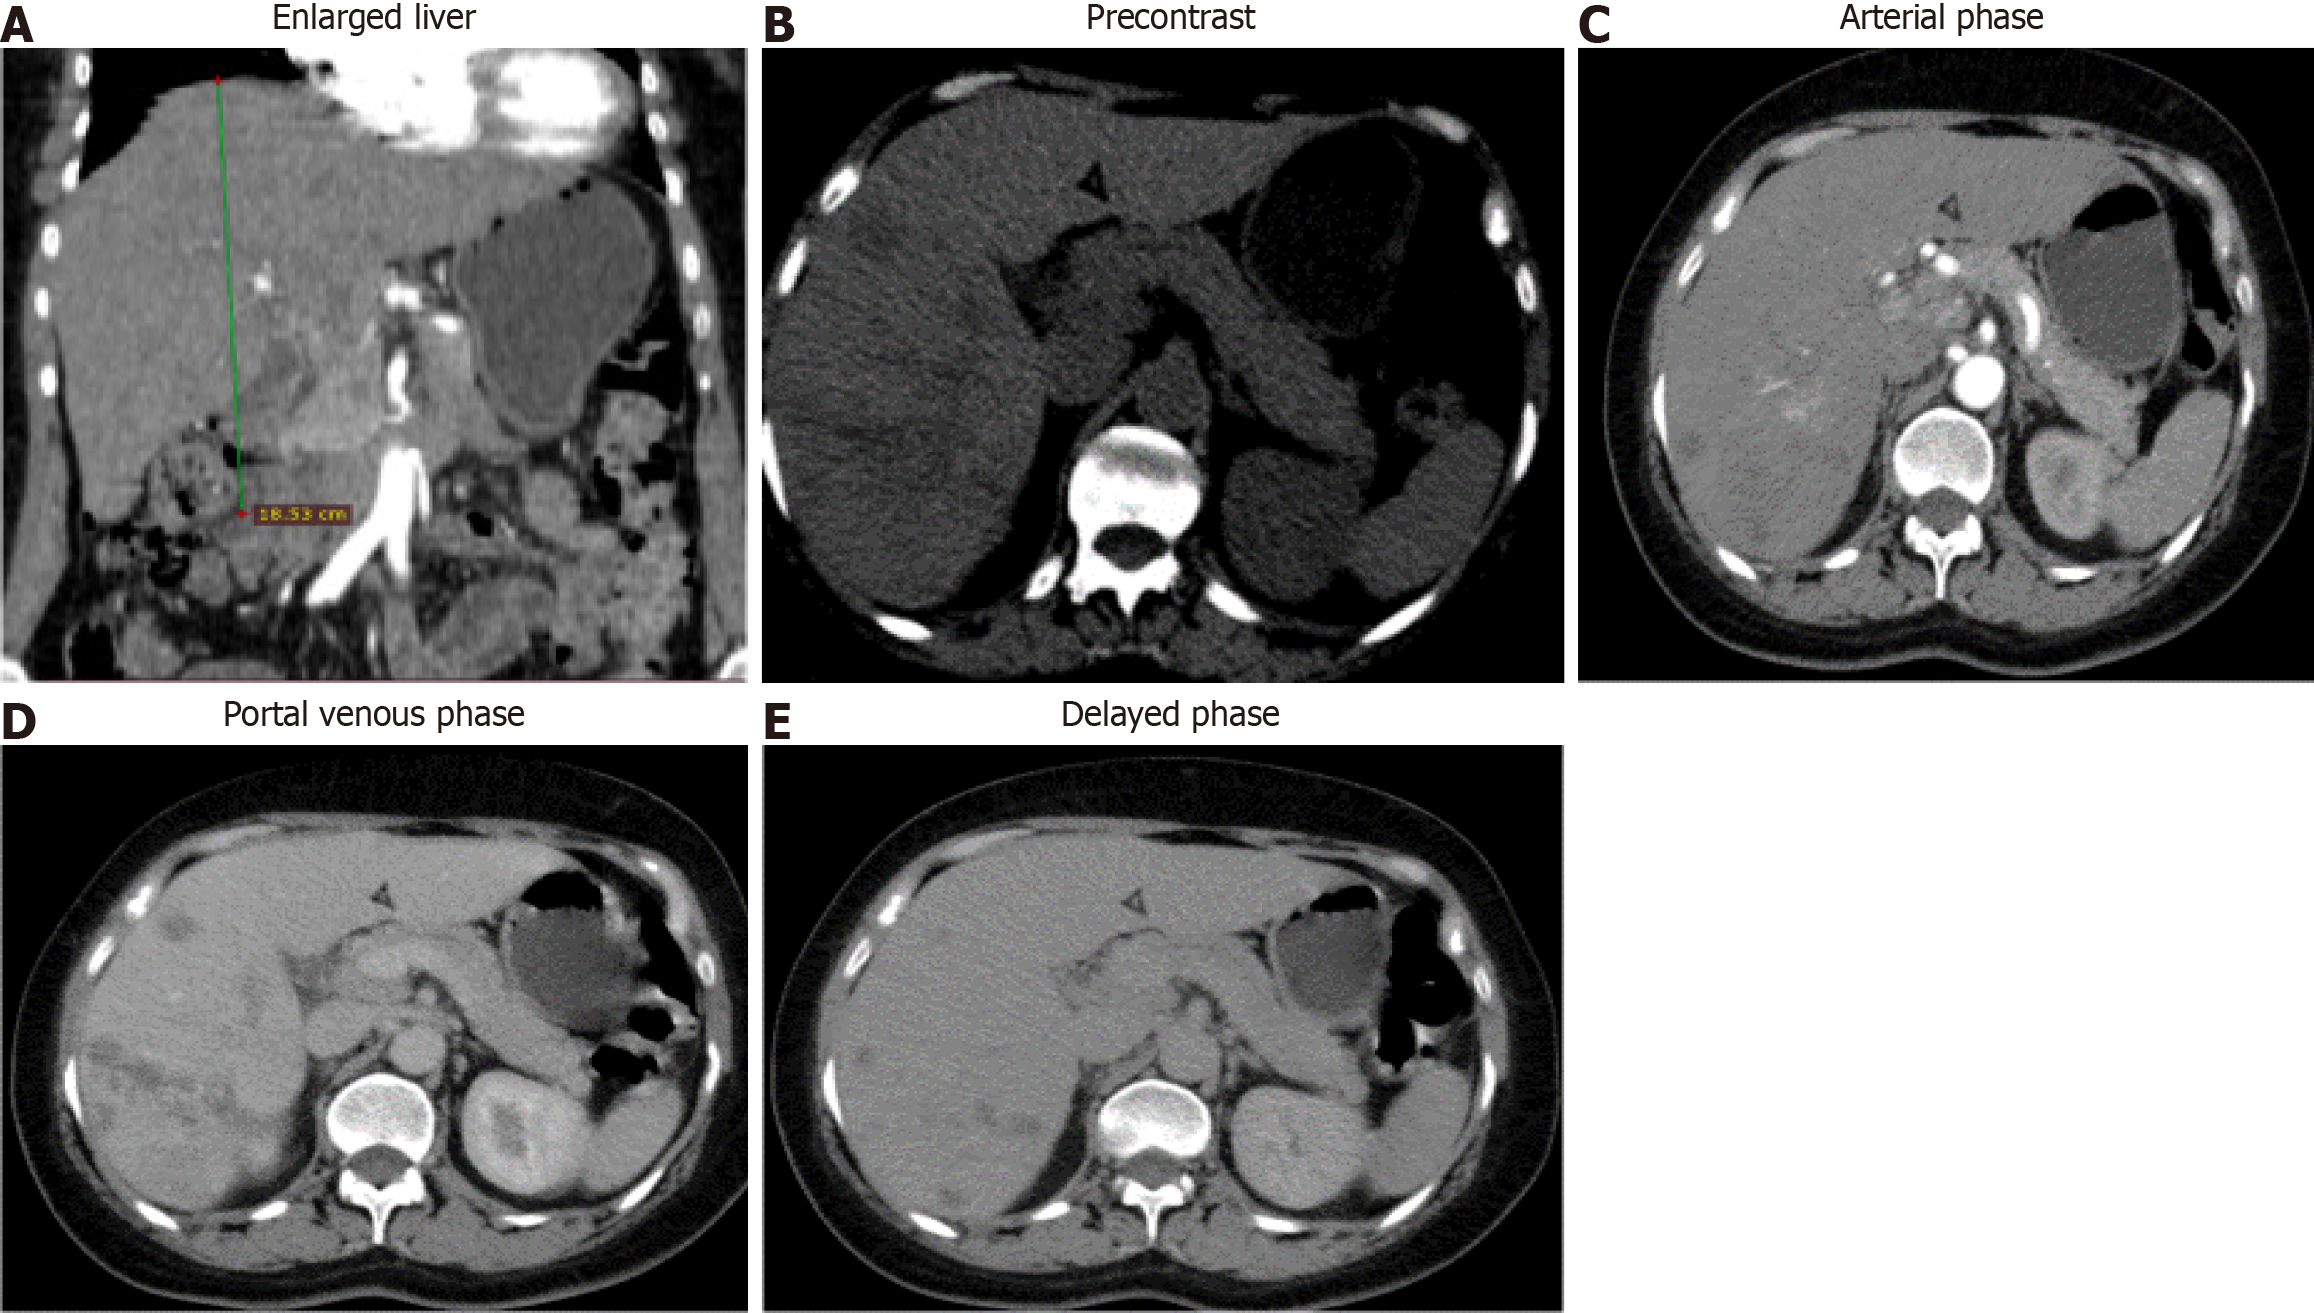

Figure 3 Abdominal computed tomography scan.

A: Abdominal computed tomography scan showed an enlarged liver; B: Shows multiple ill-defined hypodense lesions in the right lobe; C: Shows the largest lesion, a 5.3 cm × 3.3 cm measuring hypodense lesion having minimal arterial enhancement; D: Shows the delayed portal venous phase; E: Shows a slight filling in the delayed phase with the underlying hepatic parenchyma having internal attenuation more around the periportal area, which was consistent with fascioliasis.